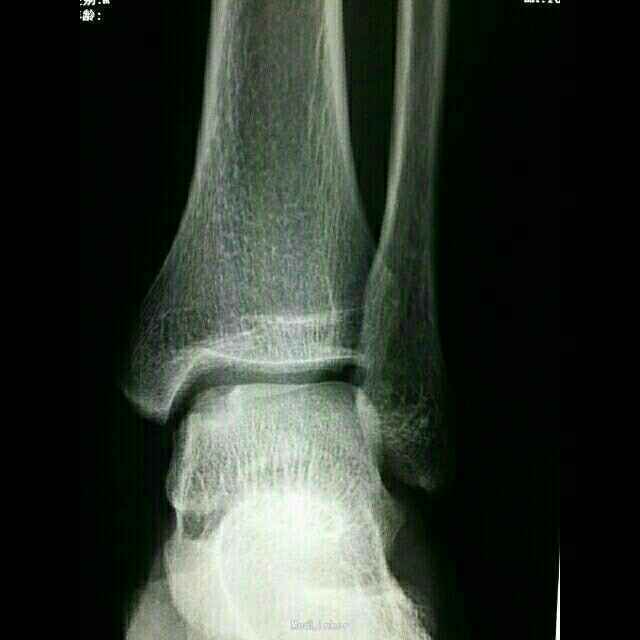

主诉:左踝关节扭伤后肿痛5天。 病史:患者男,20岁,从约1.5米高处跳下后致左踝肿痛,活动受限,当时未做特殊处理。次日感症状持续存在,且出现局部淤青,予以冰敷,云南白药气雾剂等处理,症状无明显缓解,遂来本院就诊。

查体:左足背皮下淤血,外踝及足背肿胀明显,局部压痛,活动受限,未及骨擦感。 辅助检查:左距骨囊性变并死骨形成,考虑距骨无菌性坏死可能。CT及MRI检查支持该诊断。

诊断: 1.左距骨无菌性坏死; 2.左踝急性创伤性滑膜炎。 治疗: 1.加强休息,患肢制动; 2.活血化瘀,对症支持治疗; 3.局部理疗。